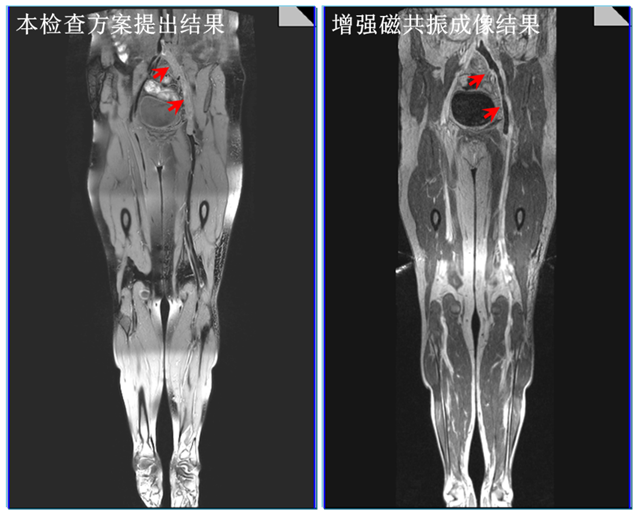

1. 本检查方案与传统静脉造影增强检查方法的成像结果比较,本方案不仅可以实现血栓分布的精准检查,还可以直接观测到血栓信号。